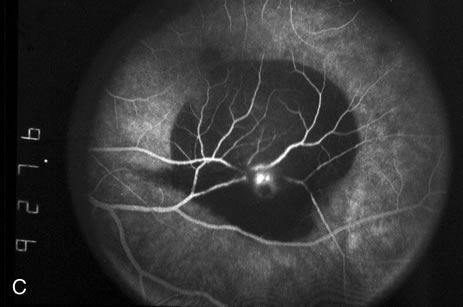

Retinal arterial macroaneurysms often produce retinal edema, circinate hard exudates, and hemorrhage (Fig. 3) into multiple layers of the retina: beneath the retinal pigment epithelium, beneath the retina, within the retina, beneath the internal limiting membrane, between the retina and the posterior hyaloid, and within the vitreous cavity. When the macroaneurysm is obscured by overlying blood, its diagnosis can be challenging.

Fig. 3. A. Color fundus photograph of a macroaneurysm along the inferotemporal arcade with surrounding intraretinal and subretinal hemorrhage. There is retinal edema, hard exudates, and thin subretinal hemorrhage extending into the macula. B. Midphase fluorescein angiography reveals hemorrhage that extends just into the foveal avascular zone, threatening foveal vision. C. Late-phase angiogram reveals staining of the macroaneurysm. D. Color fundus photograph of the same macroaneurysm 6 weeks after laser photocoagulation, demonstrating resolution of the edema and hemorrhage.

Because of rapid blood flow through retinal arterial macroaneurysms, they typically fill quickly in the early phase of the fluorescein angiogram. In the mid- and late-phases of the angiogram, the macroaneurysm tends to leak to varying degrees, depending on its perfusion and endothelial integrity (Fig. 3C). If there is subretinal fluid surrounding the aneurysm, there may be pooling of dye into the subretinal space. In some cases, a characteristic Z-shaped kink may be identified at the site of the aneurysm.

Perfusion abnormalities caused by the macroaneurysm cause changes in the surrounding retinal vasculature as well, and this is best visualized on fluorescein angiography (Fig. 3B). Ischemia from stagnation of blood flow results in capillary telangiectasis, microaneurysm formation, and capillary nonperfusion.

Some or all of these angiographic features may be obscured by blood or lipid exudation from the aneurysm. If blood collects in front of the retinal vessels (vitreous hemorrhage, preretinal hemorrhage, subinternal limiting membrane hemorrhage, or intraretinal hemorrhage), then blockage of hyperfluorescence may be partial or complete. Subretinal blood blocks hyperfluorescence from the choroid but not the retinal circulation, resulting in dramatically distinct retinal vessels against a dark background (Fig. 3B,C). Lipid exudation and retinal edema may cause partial blockage of hyperfluorescence.